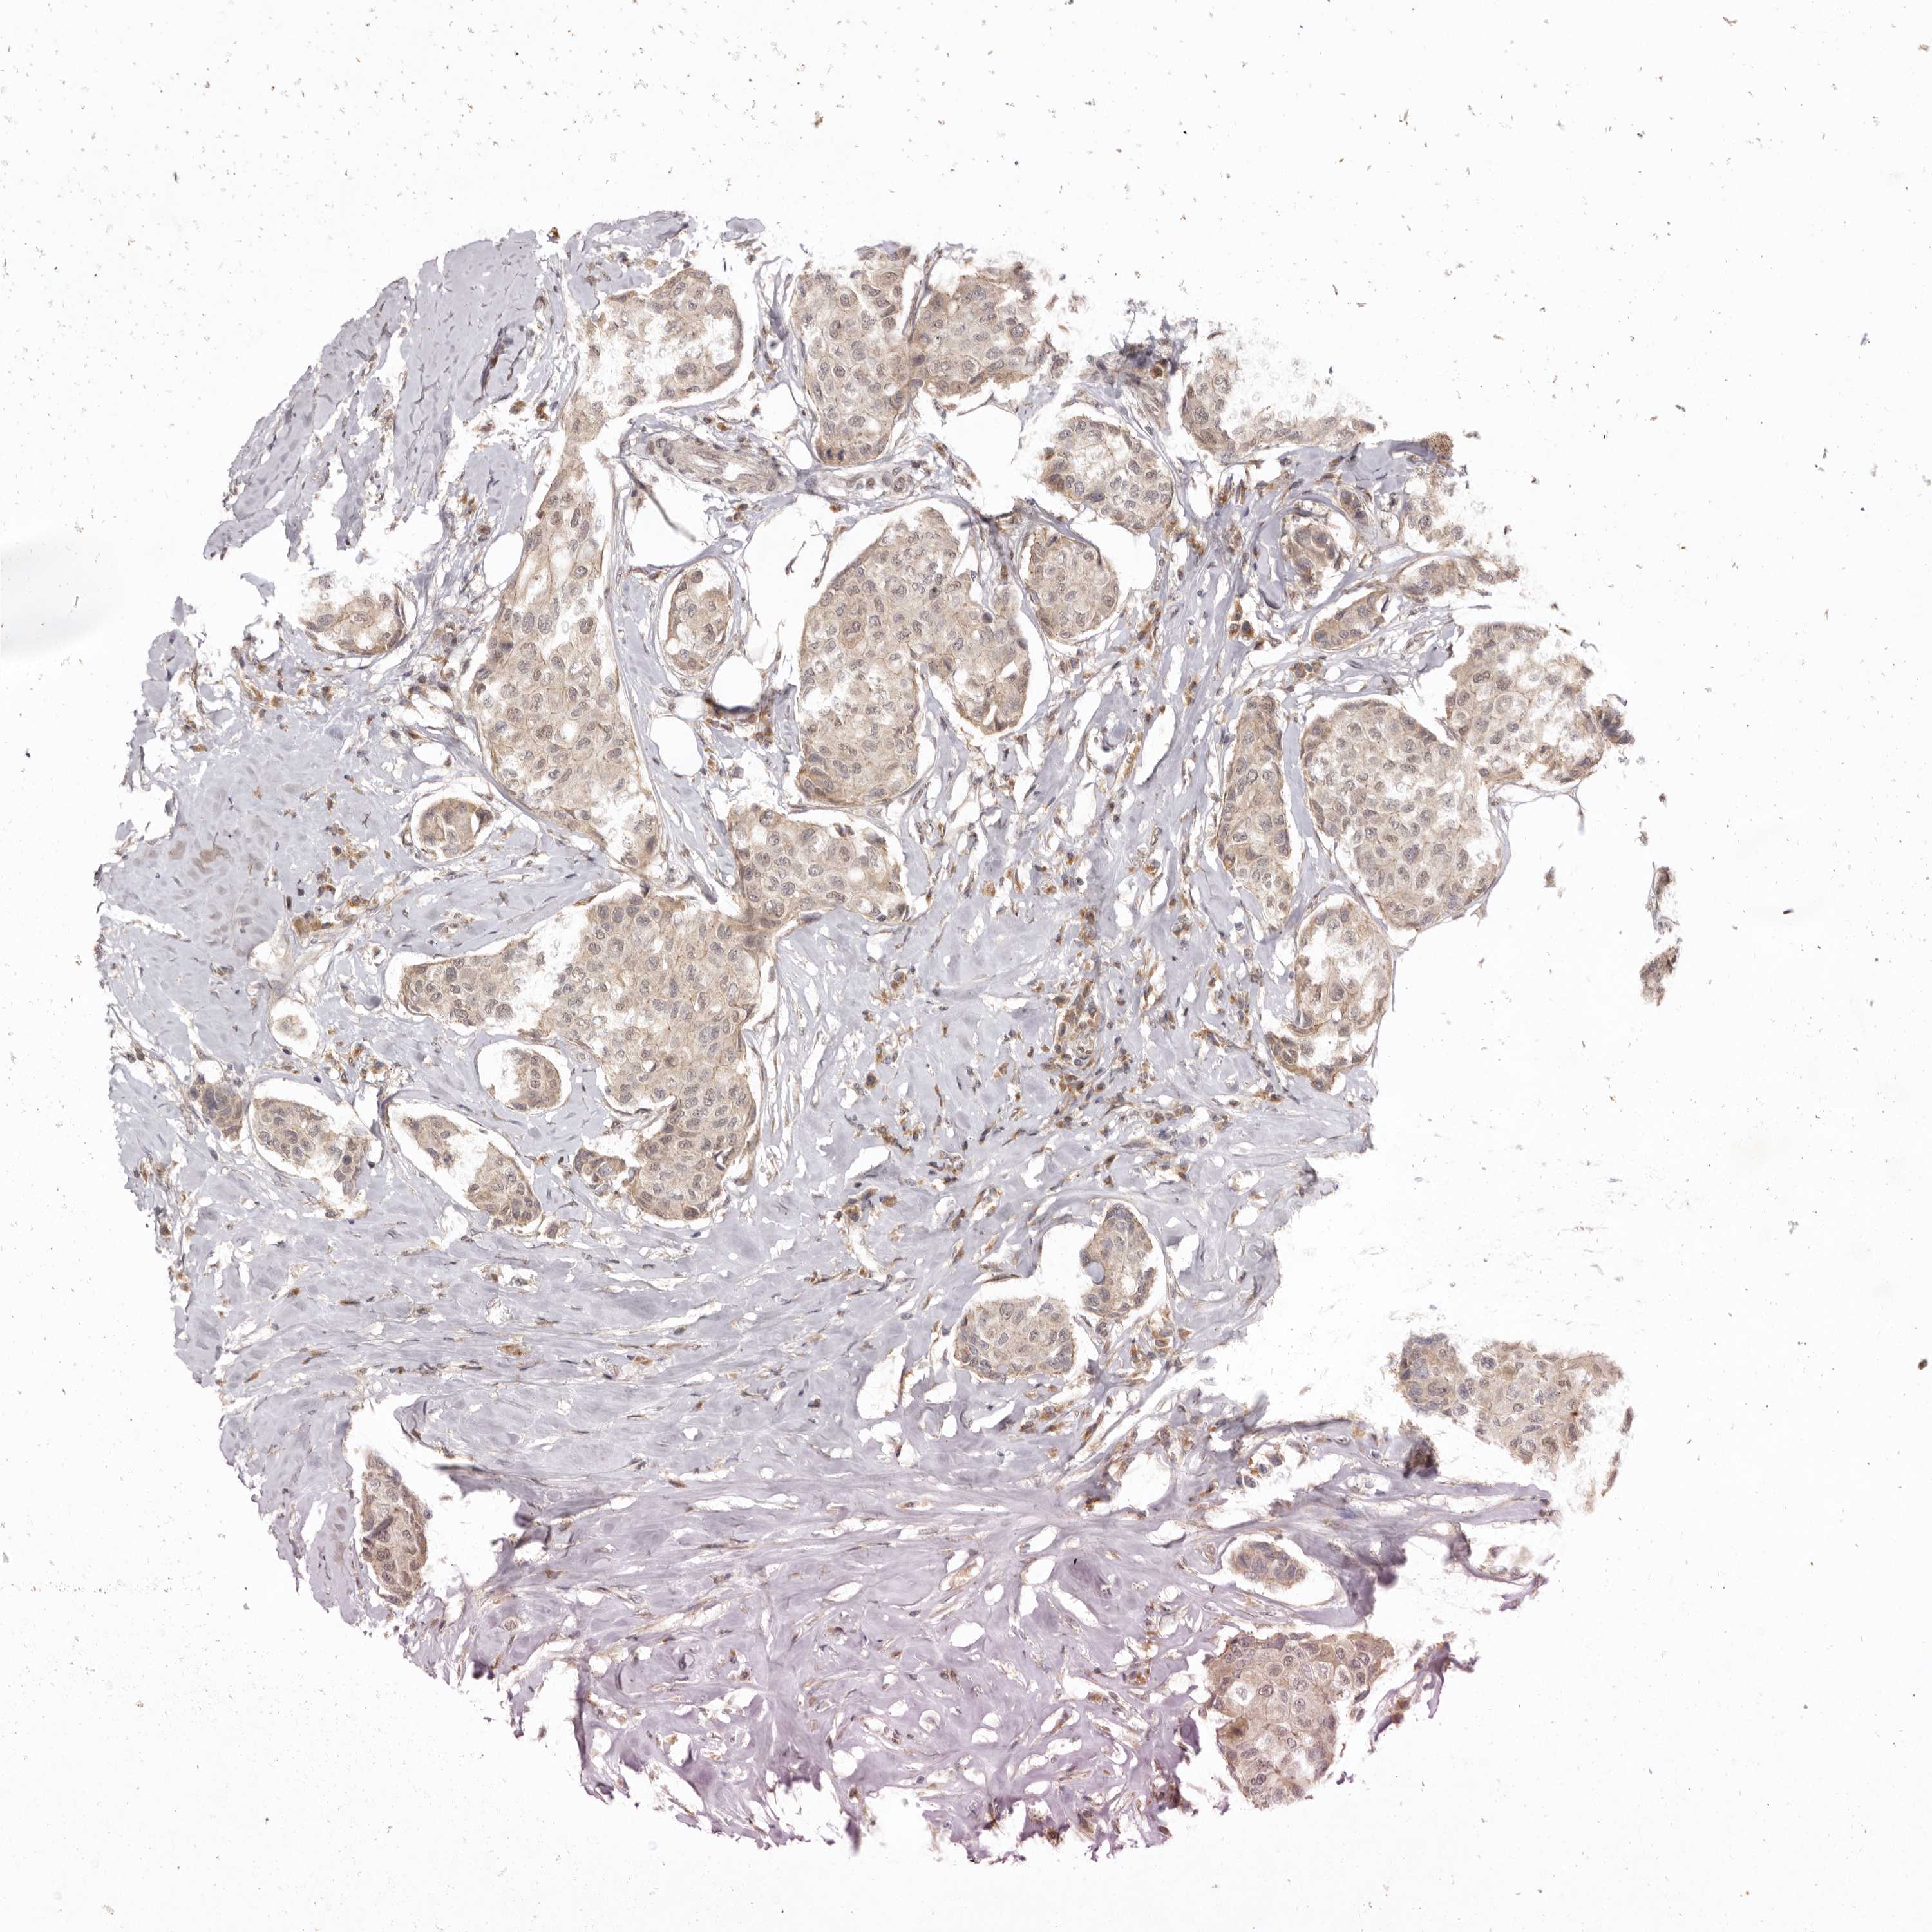

CANCER BREAST CANCER Show tissue menu

BRCA TCGA BRCA VALIDATION PROTEIN EXPRESSION

ANTIBODIES

AND

VALIDATION